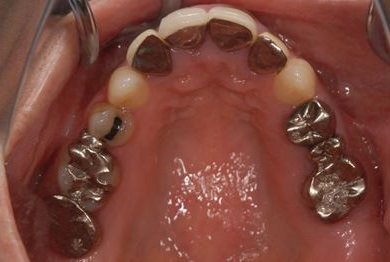

| 性別/年齢 | 女性 / 38歳 | ||||||||||||||||||||||||||||||||

| 主訴 | 奥歯の痛み(虫歯)。銀歯の所だと思います。なるべく痛くない治療がいいです。 | ||||||||||||||||||||||||||||||||

| 治療方針 | セラミック治療にて、審美的回復を行う。 | ||||||||||||||||||||||||||||||||

| 治療内容 | ハイブリッドセラミッククラウン1本(ハイブリッドセラミック用土台1本) | ||||||||||||||||||||||||||||||||

| 総治療費 | 96,600円 | ||||||||||||||||||||||||||||||||

| 治療期間 | 2ヶ月 |